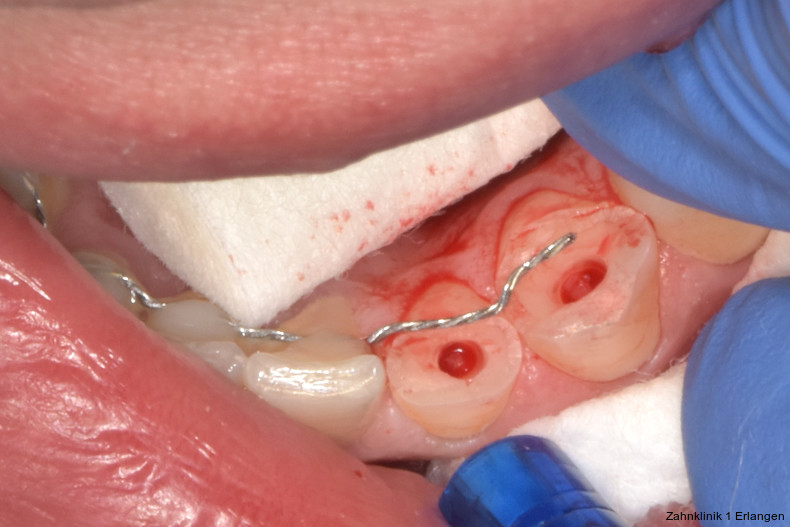

Bei Pulpaexposition ist die oberste Prämisse der Erhalt der Vitalität des Zahnes. Vor allem bei jungen Patienten und bei nicht abgeschlossenem Wurzelwachstum, aber auch bei erwachsenen Patienten ist die Vitalerhaltung die Methode der Wahl. Dabei spielen die Dauer und die Größe der Exposition keine wesentliche Rolle.10 Die oberste Gewebeschicht sollte zunächst im Sinne einer Mikropulpotomie angefrischt werden, was mit einem Diamantschleifer unter Wasserkühlung durchgeführt werden kann. Nach Blutstillung, zu der Natriumhypochlorit tropfenweise appliziert werden kann, wird das Sistieren der Blutung kontrolliert. Ist dies verifiziert, wird ein biokompatibles Material in direktem Kontakt mit dem Gewebe aufgebracht und der Zahn anschließend adhäsiv verschlossen.10 Dauert die Blutung an, beispielsweise weil der Unfall bereits mehr als 24 Stunden zurückliegt, kann tiefer pulpotomiert werden. Da eine traumatisch geschädigte Pulpa in der Regel vor dem Unfall gesund war, ist die Heilungskapazität meist sehr gut.11 Auch bei bestehender Exposition zur Mundhöhle hin über einen Zeitraum von Tagen kann die Pulpotomie noch hohe Erfolgsraten erzielen.

Tierexperimentelle Studien konnten zeigen, dass selbst bei über mehrere Tage hinweg freiliegender Pulpa Bakterien aus der Mundhöhle nicht tiefer als 2 mm in das Gewebe eindringen konnten.12 Kritisch ist dabei die erfolgreiche Blutstillung, die nach ca. fünf Minuten erreicht sein sollte. Die Erfolgsquoten der Pulpotomie nach Zahntrauma liegen deutlich über denen der direkten Überkappung bei über 90 Prozent. Dies ist auch in der revidierten Fassung der S2k-Leitlinie zum dentalen Trauma bleibender Zähne herausgestellt.3 Es ist zu beachten, dass bei begleitender Dislokationsverletzung die Durchblutung der Pulpa eingeschränkt oder sogar komplett unterbunden sein kann, was das Risiko des Misserfolges vitalerhaltender Maßnahmen signifikant erhöht.13 Daher sollte in solchen Fällen die Pulpektomie durchgeführt werden. Dies gilt ebenso bei umfangreichem Hartsubstanzverlust, wenn die definitive Restauration zusätzlich intrakanalär verankert werden muss.